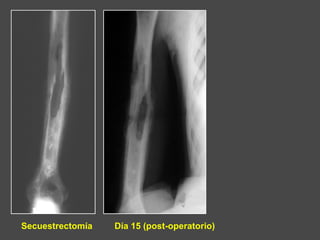

Secuestrectomía Día 15 (post-operatorio)

• El tratamiento quirúrgico comprende :

- La exéresis de los secuestros

- La eliminación de todos los tejidos necróticos,

conservando solamente al tejido sano

• El hueso puede quedar expuesto debido a los

lavados repetidos

• La cicatrización espontánea en llamada “dirigida”

Tratamiento